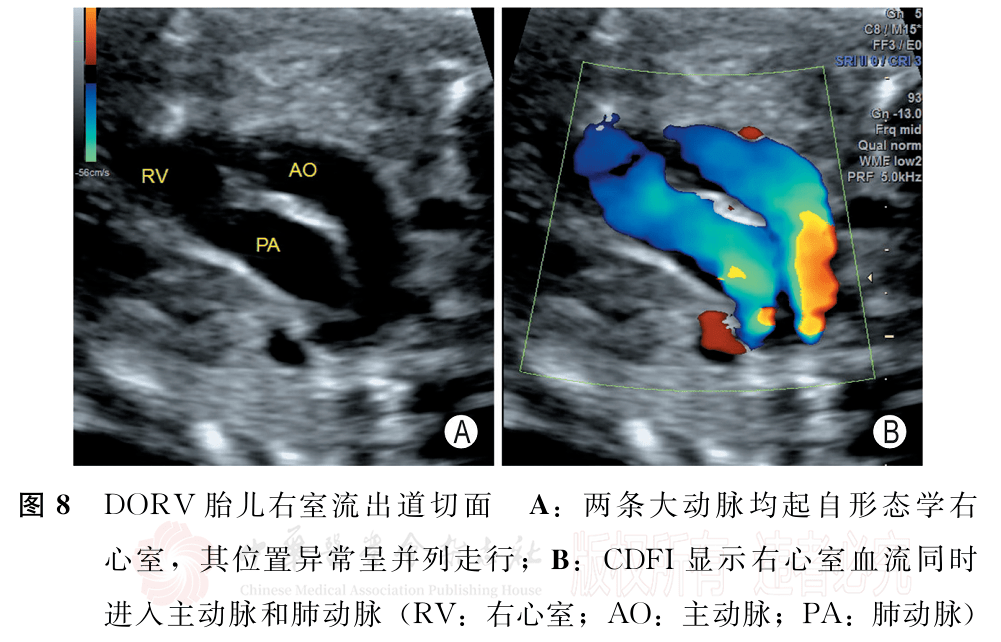

胎儿法洛四联症和右室双出口超声检查中国专家共识(2022版)(二)